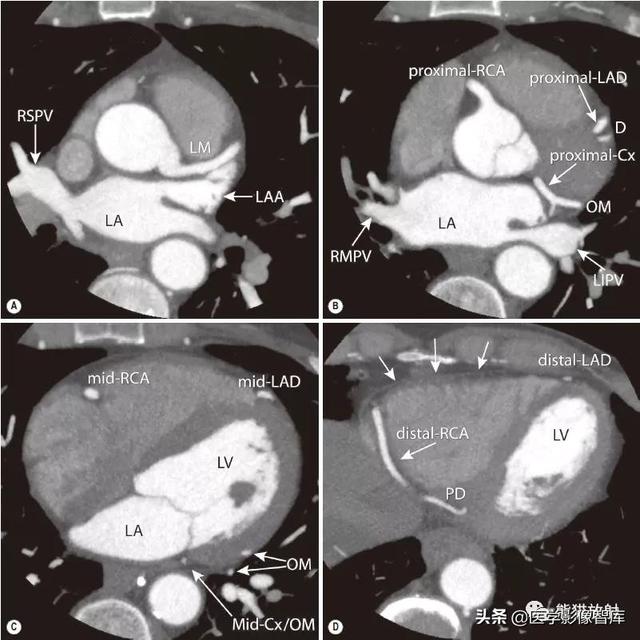

图2 冠状动脉解剖分段

横断位重建显示A、左冠状动脉主干(LM) ;B、右冠状动脉(RCA) 近段,左前降支(LAD) 近段和对角支(D) ,以及回旋支(Cx) 近段和钝缘支(OM) ;C、LAD中段,RCA中段和Cx/OM中段;D、RCA远段和后降支(PD) ,LAD远段。心包显示为细线状(D,箭) 。

所示肺静脉:LIPV-左下肺静脉;RMPV-右中肺静脉;RSPV-右上肺静脉。LA-左心房;LAA-左心耳;LV-左心室